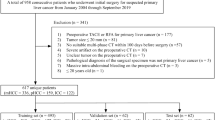

The B-mode ultrasound images of 465 patients with primary liver cancer were enrolled in model construction, comprising 264 HCCs, 105 ICCs, and 96 cHCC-ICCs, of which 50 cases were randomly selected to form an independent test cohort, and the rest of study population was assigned to a training and validation cohorts at the ratio of 4:1. Four deep learning models (Resnet18, MobileNet, DenseNet121, and Inception V3) were constructed, and the fivefold cross-validation was adopted to train and validate the performance of these models. The following indexes were calculated to determine the differential diagnosis performance of the models, including sensitivity, specificity, accuracy, positive predictive value (PPV), negative predictive value (NPV), F-1 score, and area under the receiver operating characteristic curve (AUC) based on images in the independent test cohort.